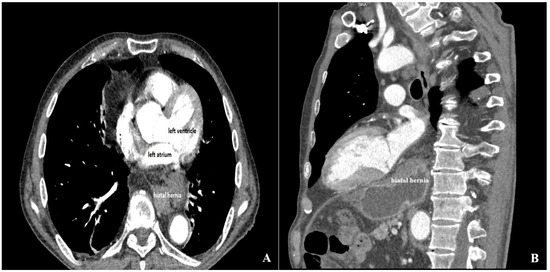

Open AccessReview

Extrinsic Left Atrial Compression: An Echocardiography-Guided Diagnosis Illustrated by Two Clinical Cases and a Structured Review of Published Cases

by

Angelina Borizanova, Elena Kinova, Semra Beyti, Todor Angelov, Plamen Getsov and Assen Goudev

J. Clin. Med. 2026, 15(7), 2611; https://doi.org/10.3390/jcm15072611 (registering DOI) - 29 Mar 2026

Abstract

Background: Extrinsic compression of the left atrium (LA) is a rare and underrecognized condition that may result in significant hemodynamic compromise and atrial arrhythmias. The available evidence has been largely limited to isolated case reports and small case series, and clinical awareness

[...] Read more.

Background: Extrinsic compression of the left atrium (LA) is a rare and underrecognized condition that may result in significant hemodynamic compromise and atrial arrhythmias. The available evidence has been largely limited to isolated case reports and small case series, and clinical awareness has remained low. Methods: We performed a structured review of published case reports and case series indexed in PubMed between 2016 and 2026 describing extracardiac LA compression. A predefined and reproducible literature search strategy with explicit eligibility criteria was applied. The structured review included 22 publications reporting 23 individual cases of LA compression; in addition, two institutional cases with distinct etiologies were presented separately. Demographic characteristics, presenting symptoms, diagnostic modalities, complications, management strategies, and outcomes were synthesized descriptively. Results: The structured review identified gastroesophageal disorders, particularly hiatal hernia, as the most frequent etiology, followed by vascular, mediastinal, malignant, and musculoskeletal causes. Dyspnea was the most common presenting symptom, while hemodynamic compromise, pulmonary edema, and atrial arrhythmia represented the most frequent complications. Transthoracic echocardiography was the initial diagnostic modality in all reported cases, with computed tomography required for definitive etiological diagnosis. The two institutional cases illustrated both a common cause, hiatal hernia mimicking intracardiac mass, and a rare, aggressive malignant cause with extensive mediastinal involvement. Conclusions: Extrinsic LA compression arises from diverse extracardiac pathologies and may be clinically severe. Transthoracic echocardiography can serve as a pivotal first-line tool for early recognition and differentiation from intracardiac masses, while cross-sectional imaging is essential for etiological clarification. By integrating institutional experience with a structured synthesis of published cases, this review can provide practical insights to support timely diagnosis and management of this potentially life-threatening condition.

Full article

(This article belongs to the Section Cardiology)